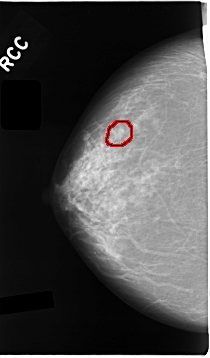

C_0024_1.RIGHT_CC

FILE: C_0024_1.RIGHT_CC.OVERLAY

TOTAL_ABNORMALITIES 1

ABNORMALITY 1

LESION_TYPE MASS SHAPE LOBULATED MARGINS CIRCUMSCRIBED

ASSESSMENT 3

SUBTLETY 5

PATHOLOGY BENIGN

TOTAL_OUTLINES 1

BOUNDARY